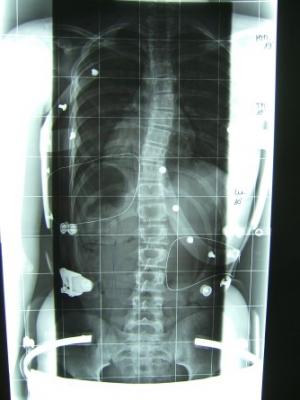

Hier sind Kokos Bilder!

Die Korrekturwerte sind wie folgt: Von lumbal 25° auf 10°, (60%),

von thorakal 26° auf 18°, (~30%),

neu dazugekommen, aber laut Herr Rahmouni zu vernachlässigen: hochthorakal 19°

Wir hatten um ein gut tragbares Korsett gebeten, das ist es auch geworden.

Wohl deshalb, und auch weil bei Koko die Skoliose genau anders herum gebogen ist wie in 95% der Fälle, sind die Werte nicht sooo toll...

Was meint ihr, muss da sofort mehr Druck drauf, und was ist das mit dem hochthorakalen Bogen, hat sich sowas bei euch auch im Korsett entwickelt?

forum_photo-röntgen mit korsett.jpg

forum_photo-röntgen mit korsett.jpg (17.37 KiB) 12998 mal betrachtet